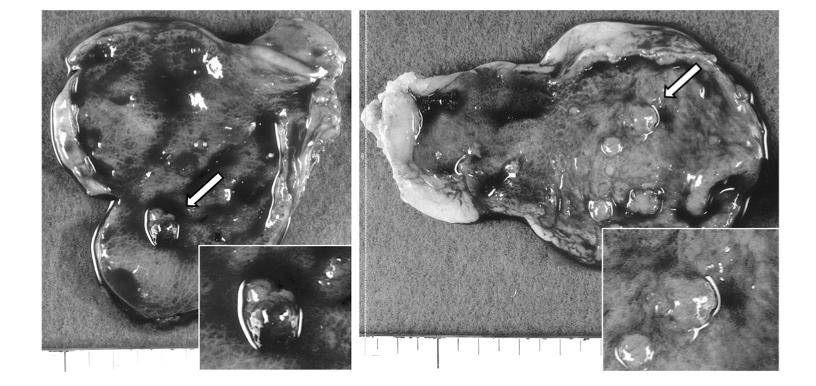

常见类型四、腺瘤性息肉

胆囊腺瘤属于胆囊良性肿瘤,单发多于多发,癌变概率为3–8%,癌变概率与腺瘤体积呈正相关。形态方面,胆囊腺瘤形成初期,呈乳头状,边界光整。随着胆囊腺瘤体积增大,形态逐渐变为椭圆形、菜花状,边界不光整,可见桑葚征。

图片来源:胆石症研究中心,侵权删除